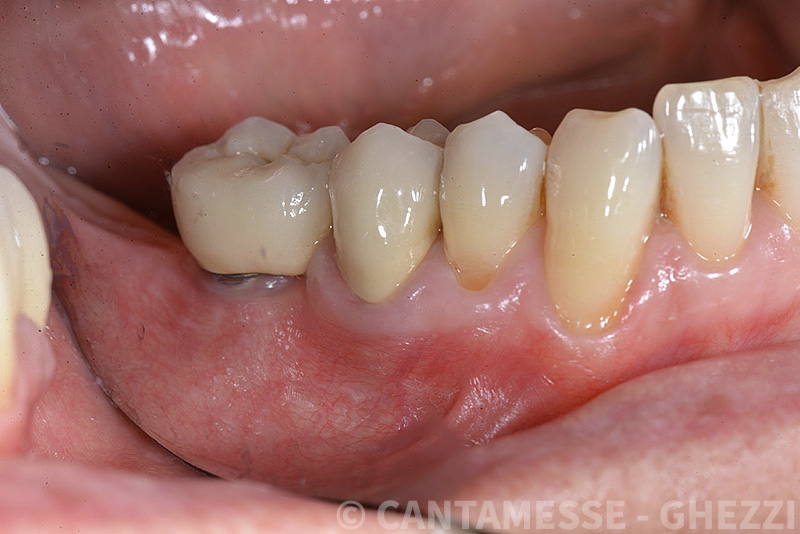

PREMESSA: in seguito all’estrazione dell’incisivo laterale superiore di destra, resasi necessaria per cause batteriche, si decide di affrontare il caso con il posizionamento di un impianto in sostituzione dell’elemento mancante dopo guarigione del sito infetto. Con tecniche rigenerative sia dei tessuti ossei mancanti a causa dell’infezione pregressa, sia dei tessuti gengivali che appaiono inizialmente troppo spostati in alto, si ripristina una corretta morfologia delle parabole (contorni) gengivali e delle papille interdentali (triangoli di gengiva tra due denti vicini).

Vengono utilizzati 2 tipi di provvisori: il primo, cementato ai denti vicini, viene utilizzato dal momento dell’estrazione del dente fino ad impianto osteointegrato (circa 6 mesi); il secondo, avvitato direttamente all’impianto, ha una funzione di prova estetica ma soprattutto di guida per la maturazione dei tessuti gengivali peri-implantari portandoli verso la maturazione completa prima di posizionare la corona finale in disilicato di litio.